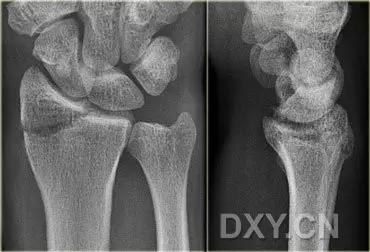

手腕部骨折

2. Colles 骨折

桡骨远端骨折,伴有桡骨远端向背侧的移位,可以有或没有尺骨干的骨折。具有这几个特征:背侧粉碎、向背侧成角、向背侧移位且挠骨短缩的关节外骨折。

典型 colles 骨折,枪刺样、餐叉样畸形